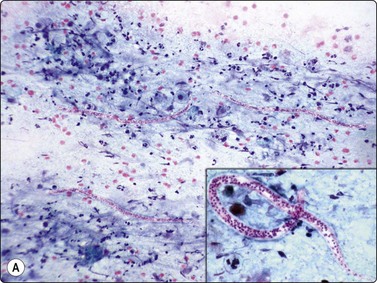

image image image

Fig. 18.19 Filariasis due to Dirofilaria repens

(A) With multiple microfilariae in background of neutrophils, with blunt heads and tapered rear ends (insert) (Pap, ×200); (B) Aggregated eggs (Pap, ×400); (C) Adult gravid female in background of eosinophils, from FNB of ‘malignant’ breast lesion (Pap, ×200).

(Figures 19A, 19B Courtesy Dr Khosrow Daneshbod, Shiraz, Iran; Figure 19C Courtesy Dr Roy, Mumbai, India)